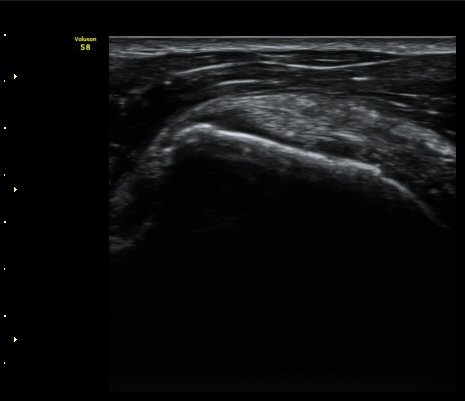

±Ø»ó°Ç ³»Ãø Á¾´Ü¸é°Ë»ç¿¡¼­ ƯÀÌ ¼Ò°ßÀ» º¸ÀÌÁö ¾ÊÀ¸³ª(»çÁø 4)

±Ø»ó°Ç ¸»´ÜºÎ¿Í ºÎÂøºÎ¿¡¼­ ÈûÁÙÀÇ ±¹¼ÒÀû Àú¿¡ÄÚ °á¼ÕÀÌ °üÂûµÈ´Ù(»çÁø 7, 8).